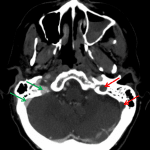

- Multiple areas of segmental thrombus in the nondominant left transverse sinus with occlusive thrombus extending from the transverse-sigmoid sinus junction into the left internal jugular vein

- Lack of opacification of the bilateral cavernous sinuses

- Nonopacified, engorged left superior ophthalmic vein

- Nonocclusive filling defect in the right jugular bulb

- Dural venous and cavernous sinus thrombosis

Dural venous sinus thrombosis with multiple areas of segmental thrombus in the nondominant left transverse sinus and occlusive thrombus extending from the transverse-sigmoid sinus junction into the left internal jugular vein. Lack of opacification of the bilateral cavernous sinuses is concerning for bilateral cavernous sinus thrombosis. There is also thrombosis of the left superior ophthalmic vein and nonocclusive thrombus in the right jugular bulb. No acute hemorrhage or mass effect.